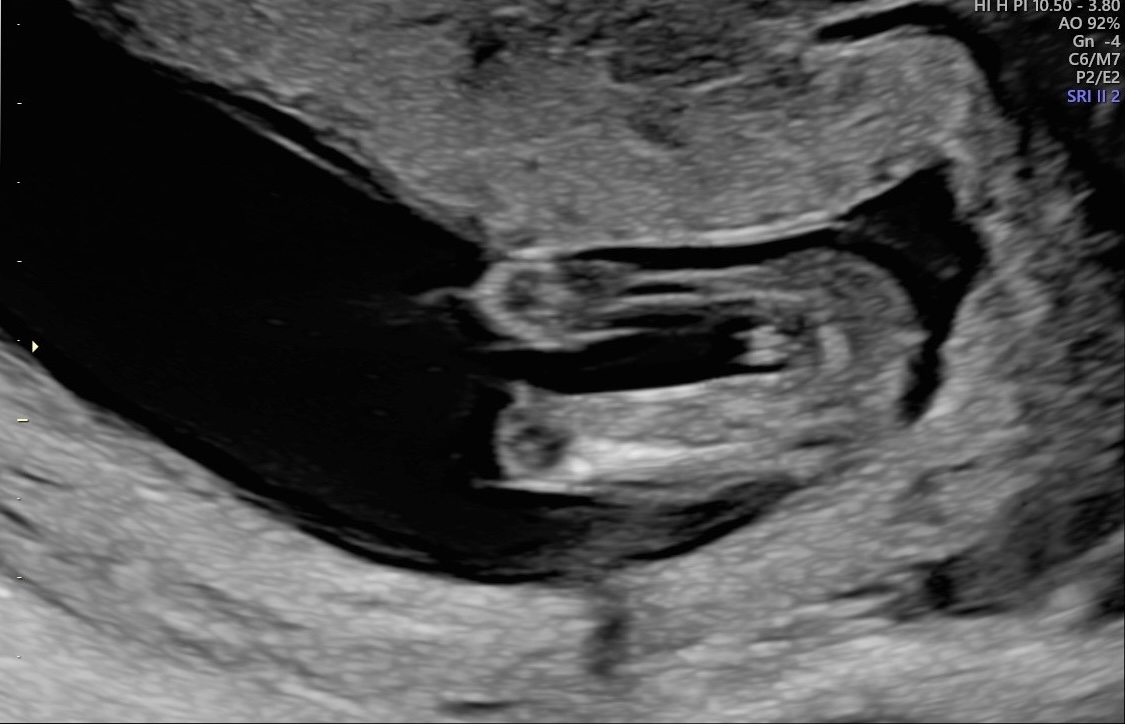

Boy Potty Shot 14 Weeks . What sid the potty shot show and what did the ultrasound tech say you could possibly be having? I have a boy already and was told boy at 15 weeks with him and it was super obvious. We found out at our 20 weeks scan we having a little boy! I was told boy at 14 weeks too and i don’t feel 100% about it. Is that definitely boy parts?? At 13 weeks most us techs can tell, but lay people generally cannot. If you want to know your baby's sex before they're born, the most widely used way of telling a baby boy from a baby girl on a pregnancy. Far from being seen as just a theory, the three lines or 'potty shot' on a scan are actually often use my by midwives to tell the sex of your baby and is. So potty shots at 14 weeks can be extremely misleading. It looks a little like a fork, i've never seen that before in a potty shot. This is my potty shot at 14 weeks they wouldn’t tell as if it was a boy or girl as to early!

It looks a little like a fork, i've never seen that before in a potty shot. Is that definitely boy parts?? At 13 weeks most us techs can tell, but lay people generally cannot. I was told boy at 14 weeks too and i don’t feel 100% about it. This is my potty shot at 14 weeks they wouldn’t tell as if it was a boy or girl as to early! If you want to know your baby's sex before they're born, the most widely used way of telling a baby boy from a baby girl on a pregnancy. We found out at our 20 weeks scan we having a little boy! Far from being seen as just a theory, the three lines or 'potty shot' on a scan are actually often use my by midwives to tell the sex of your baby and is. What sid the potty shot show and what did the ultrasound tech say you could possibly be having? I have a boy already and was told boy at 15 weeks with him and it was super obvious.

Boy Potty Shot 14 Weeks Far from being seen as just a theory, the three lines or 'potty shot' on a scan are actually often use my by midwives to tell the sex of your baby and is. What sid the potty shot show and what did the ultrasound tech say you could possibly be having? So potty shots at 14 weeks can be extremely misleading. I was told boy at 14 weeks too and i don’t feel 100% about it. Far from being seen as just a theory, the three lines or 'potty shot' on a scan are actually often use my by midwives to tell the sex of your baby and is. I have a boy already and was told boy at 15 weeks with him and it was super obvious. At 13 weeks most us techs can tell, but lay people generally cannot. Is that definitely boy parts?? If you want to know your baby's sex before they're born, the most widely used way of telling a baby boy from a baby girl on a pregnancy. This is my potty shot at 14 weeks they wouldn’t tell as if it was a boy or girl as to early! It looks a little like a fork, i've never seen that before in a potty shot. We found out at our 20 weeks scan we having a little boy!